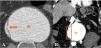

La angiografía computarizada multifásica (angio-TC) es de elección en situaciones de urgencia, permitiendo una evaluación detallada de las estructuras vasculares. La resonancia magnética, la ecografía y las técnicas de medicina nuclear pueden ser útiles en ciertos casos.

Los signos directos en angio-TC incluyen la visualización del tracto fistuloso y la extravasación de contraste, no obstante, es más frecuente identificar signos indirectos como anormalidades de la pared aórtica, engrosamiento de la grasa perivascular o colecciones. Además, hay ciertas condiciones que pueden imitar a las fístulas, lo que hace esencial un diagnóstico diferencial.

Multiphasic computed tomography angiography (CTA) is the gold standard in emergency situations, enabling a detailed evaluation of vascular structures. Magnetic resonance imaging, ultrasound and nuclear medicine techniques may be useful in certain cases.

Direct signs in CTA include visualisation of the fistulous tract and contrast extravasation. However, it is more common to identify indirect signs such as aortic wall abnormalities, perivascular fat thickening or collections. In addition, other conditions can mimic fistulae, making a differential diagnosis essential.